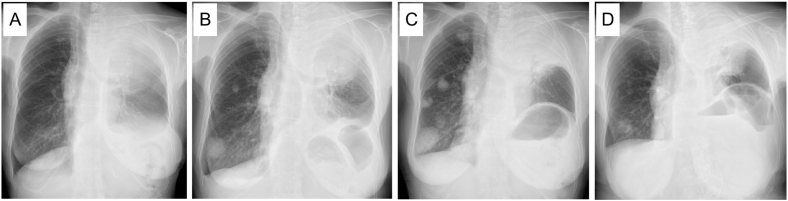

Fig. 1.

Chest X-ray findings. (A) A giant mass shadow was observed in the left upper lung field at the initial visit. (B) The pulmonary metastatic colonies in the right lung were obviously enlarged when second-line chemotherapy was introduced. F1CDx was performed at this time. (C) The lung metastatic colonies were further enlarged when osimertinib was introduced. (D) A marked anti-tumor response was observed after two months of osimertinib treatment.

Based on these findings, we started to treat her with carboplatin (area under the curve [AUC] = 5) and pemetrexed (500 mg/m2) and pembrolizumab (200 mg/body); however, she developed severe erythema multiforme (Grade 3 according to the Common Terminology Criteria for Adverse Events [CTCAE] v5.0). Therefore, we were compelled to discontinue the chemotherapy and treat her with steroids. Subsequently, the primary tumor grew and invaded the spinal canal, so we treated the patient with palliative irradiation (50 Gy), followed by S-1 (50 mg twice daily for 14 consecutive days followed by 7 days of no treatment) as second-line chemotherapy, as the pulmonary metastases had obviously grown (Fig. 1B).

When we started the second-line chemotherapy, we also performed F1CDx using the biopsied specimen at the diagnosis. Surprisingly, it detected a rare variant of EGFR exon19 deletion (S752_I759del) that was not covered by the ODxTT. Although we administered S-1 for three cycles, the metastatic nodules in her right lower lung field grew (Fig. 1C). We then treated her with osimertinib (80 mg daily), a third-generation EGFR-TKI. She showed a favorable anti-tumor response here (partial response according to the Response Evaluation Criteria in Solid Tumors [RECIST] v1.1) (Figs. 1D, and Fig. 3), and the response has continued for six months since the administration of osimertinib.